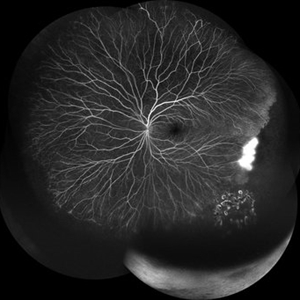

Exudative Retinal Detachment secondary to Leber's Miliary Aneurysm in a case of Retinitis Pigmentosa

Oct 13 2022 by Vaidehi Sathaye

Fundus Photograph of RE of a 23 year male patient , with an Exudative Retinal Detachment secondary to Leber's Miliary Aneurysm in a case of Retinitis Pigmentosa.

Photographer: Dr. Vaidehi Sathaye

Imaging device: Mirante

Condition/keywords: exudative detachment, Leber's miliary aneurysm, retinitis pigmentosa